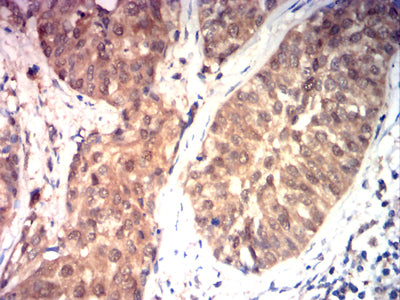

- Immunohistochemical analysis of paraffin-embedded human bladder cancer tissues using HSP70 mouse mAb with DAB staining.

- Immunohistochemical analysis of paraffin-embedded human rectal cancer tissues using HSP70 mouse mAb with DAB staining.